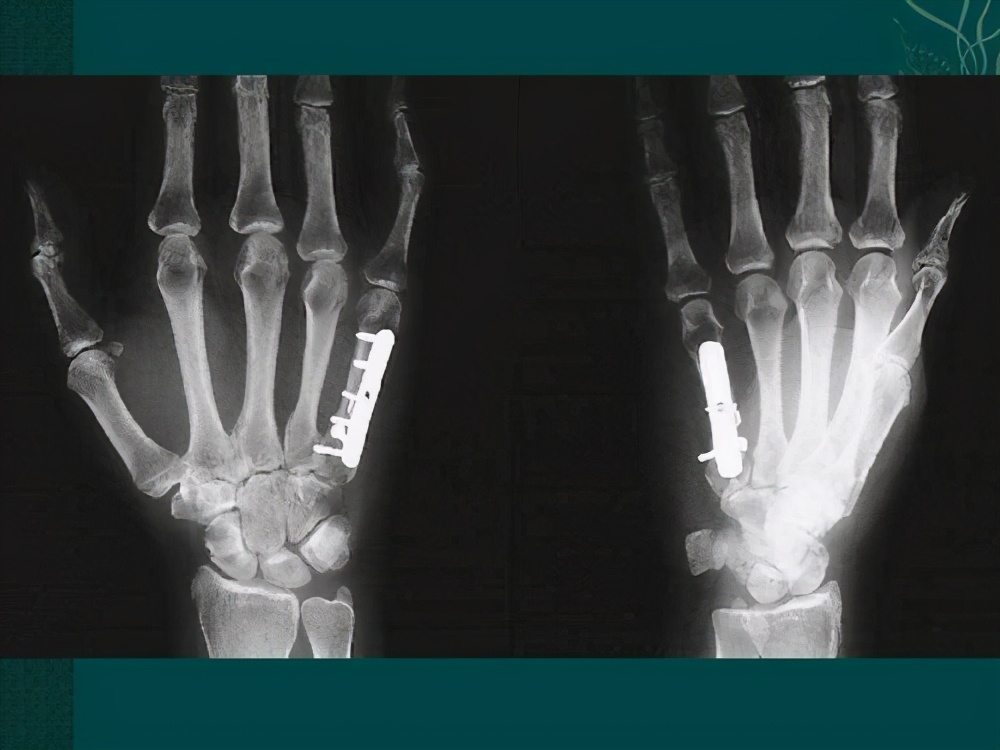

2、浅表部位:钢板就在皮下,比如一些掌骨钢板或者尺骨鹰嘴钢板, 因为钢板在这些部位容易触及,一个是摸着不舒服,另一个钢板与皮肤反复摩擦容易损伤娇嫩的皮肤。另一个主要愿意就是这样的部位取起来也相对简单,手术风险小,手术时间短,患者术后康复快。

掌骨板